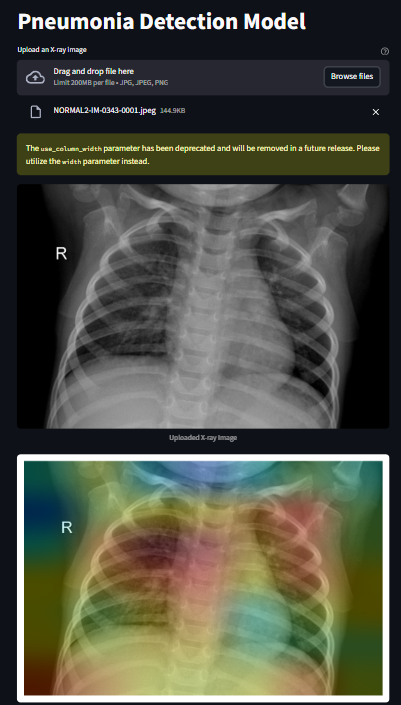

A deep learning-based medical imaging system that detects pneumonia from chest X-ray images using EfficientNet and visualizes model decisions using Grad-CAM.

The model achieves strong validation performance and provides visual explanations to improve interpretability.

• Detects Pneumonia vs Normal from chest X-rays

• Explainable AI with Grad-CAM